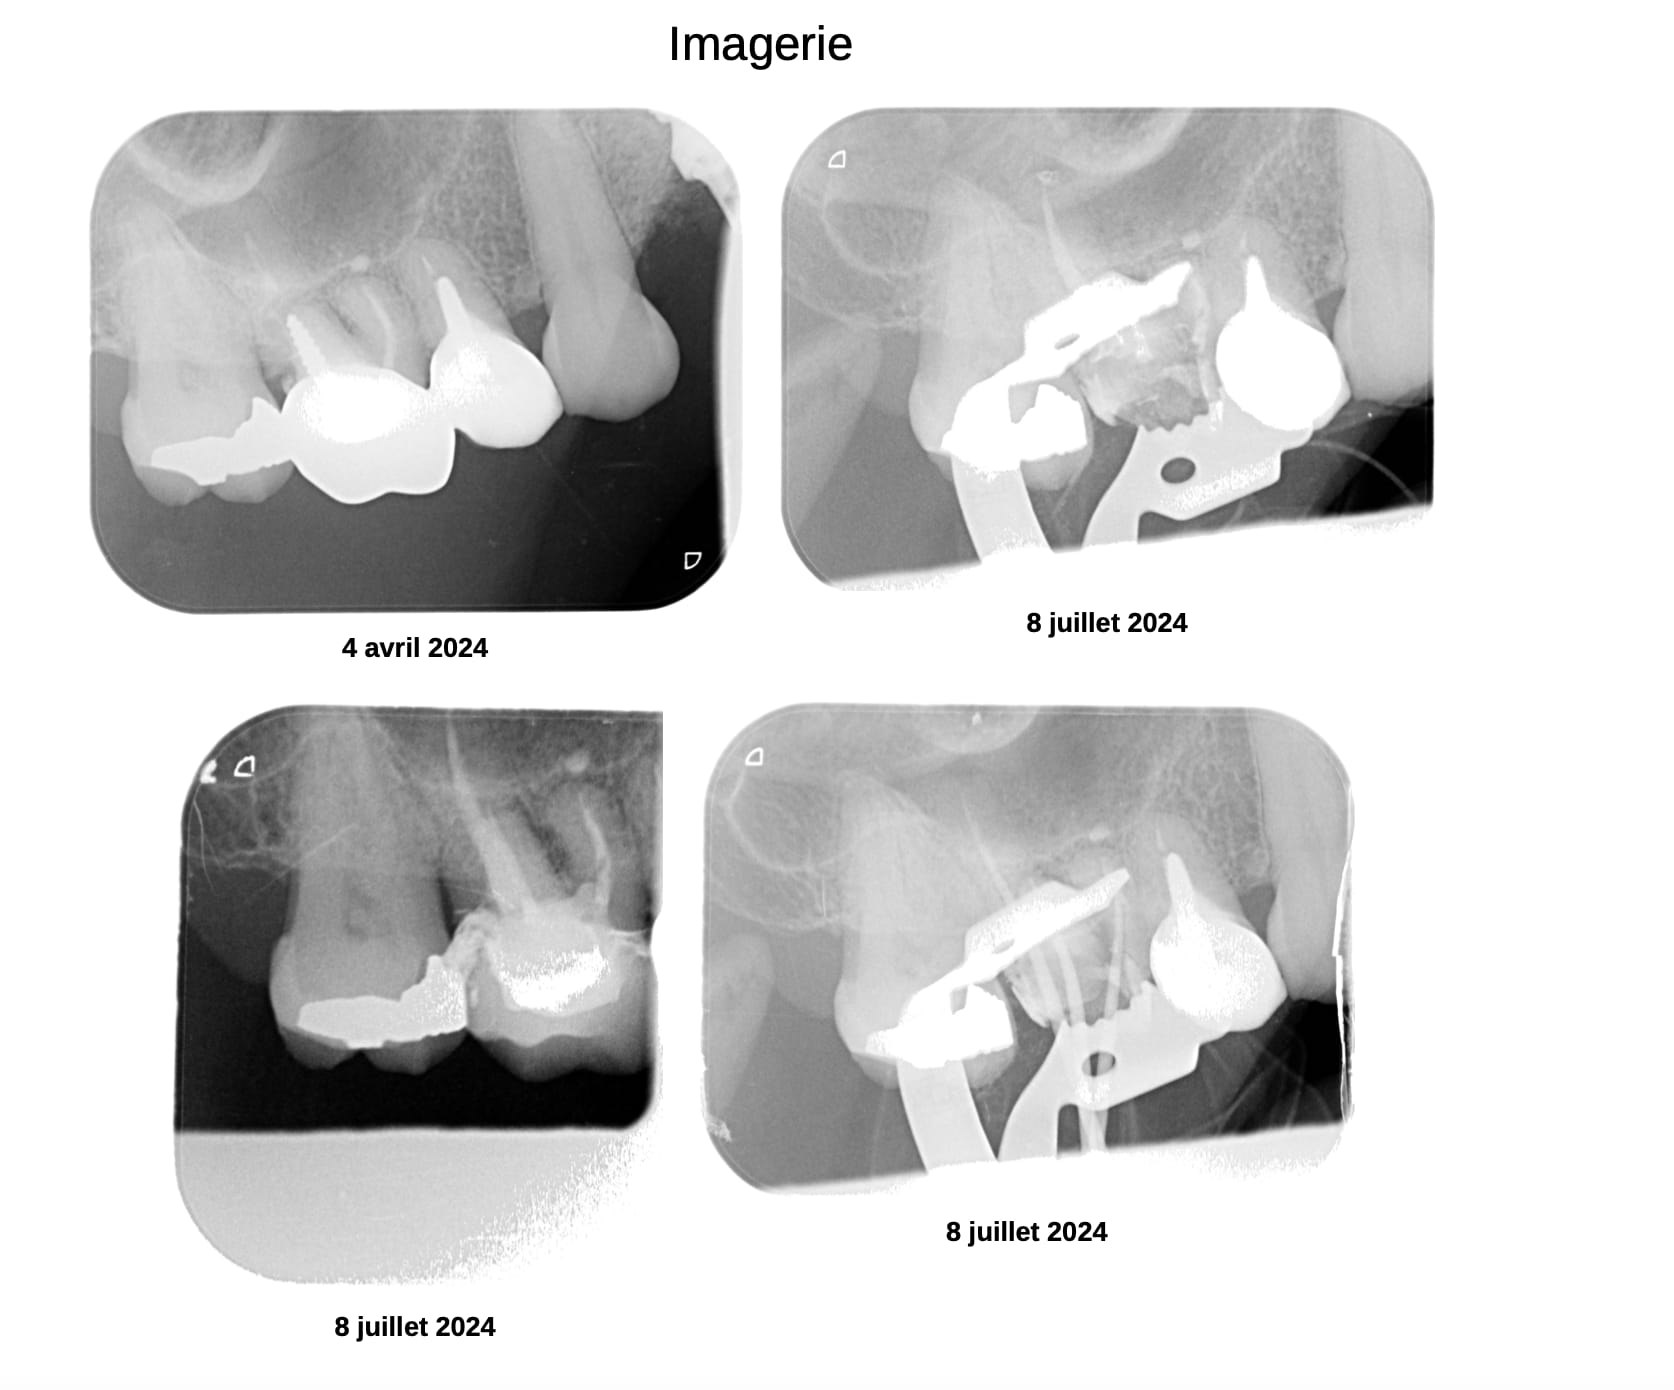

enfin la sante, quand je vois les patients que vous avez edente, je me demande si l indication des avulsions est véritablement posée... il y a beaucoup de cas que tu présentes ou la question de la mutilation peut être soulevée.